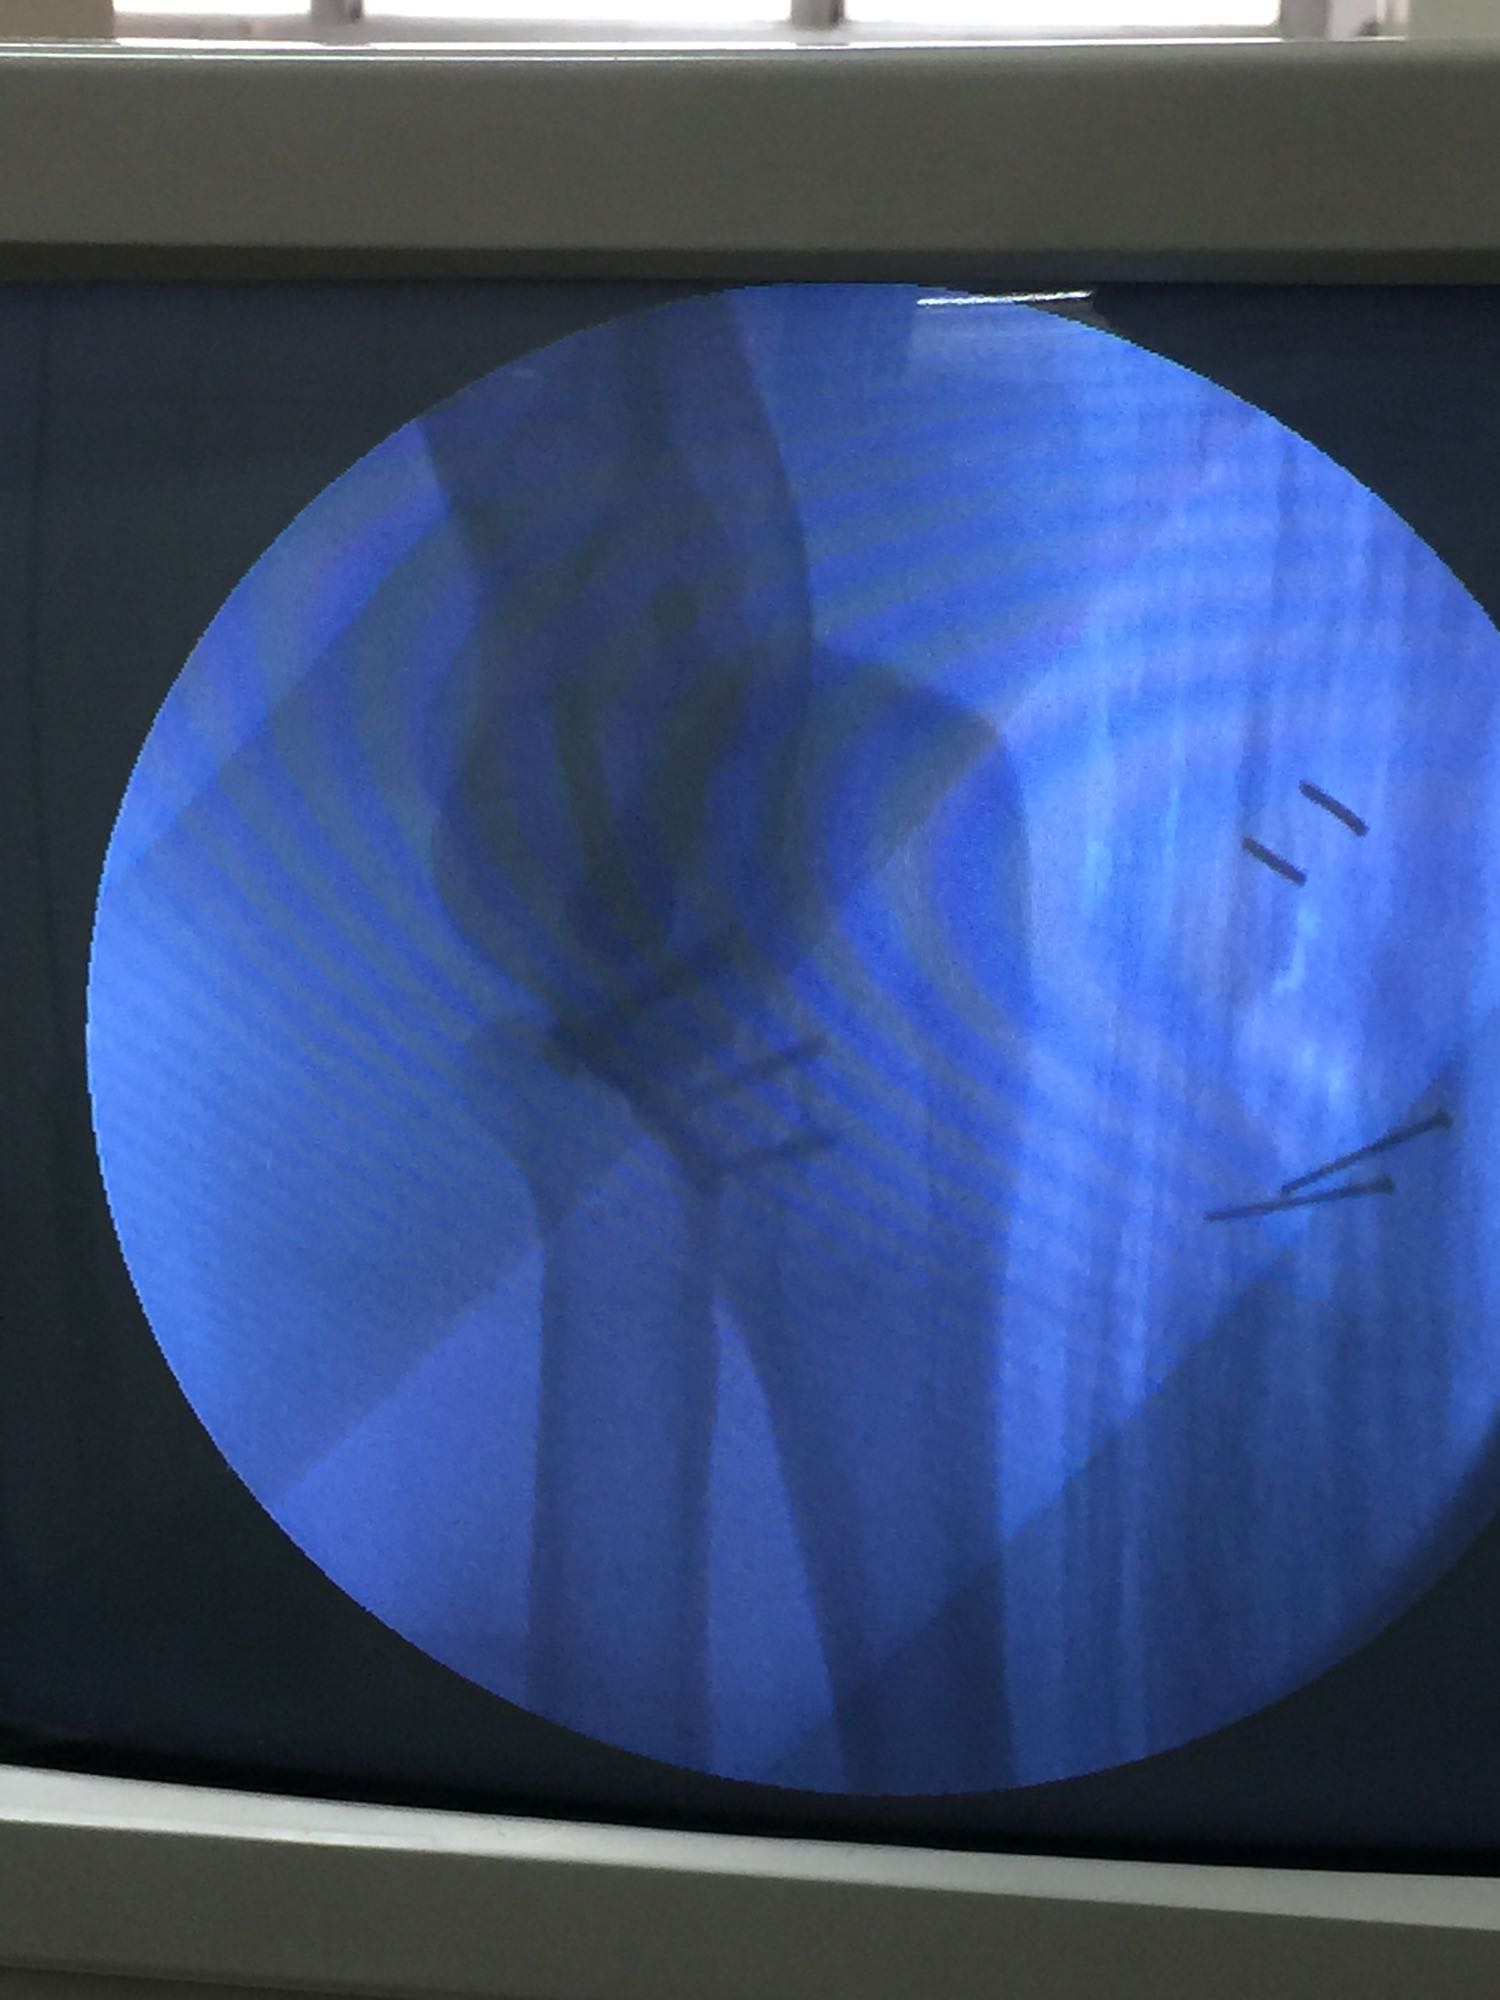

左肘关节高度肿胀,压痛强阳性,肘关节明显活动受限,末梢血运良好,各指关节运动正常。 X线片及CT如图:

1、左尺骨冠状突骨折;2、左肱骨外髁撕脱骨折 治疗:入院后伤肢石膏外固定,给予局部冷敷消肿治疗,于伤后一周行骨折手术治疗,先行前内侧切口复位固定冠状突骨折,活动肘关节发现关节明显不稳定,随取外侧切口,复位固定肱骨外髁,修补外侧副韧带,肘关节明显稳定。术中术后片子如下